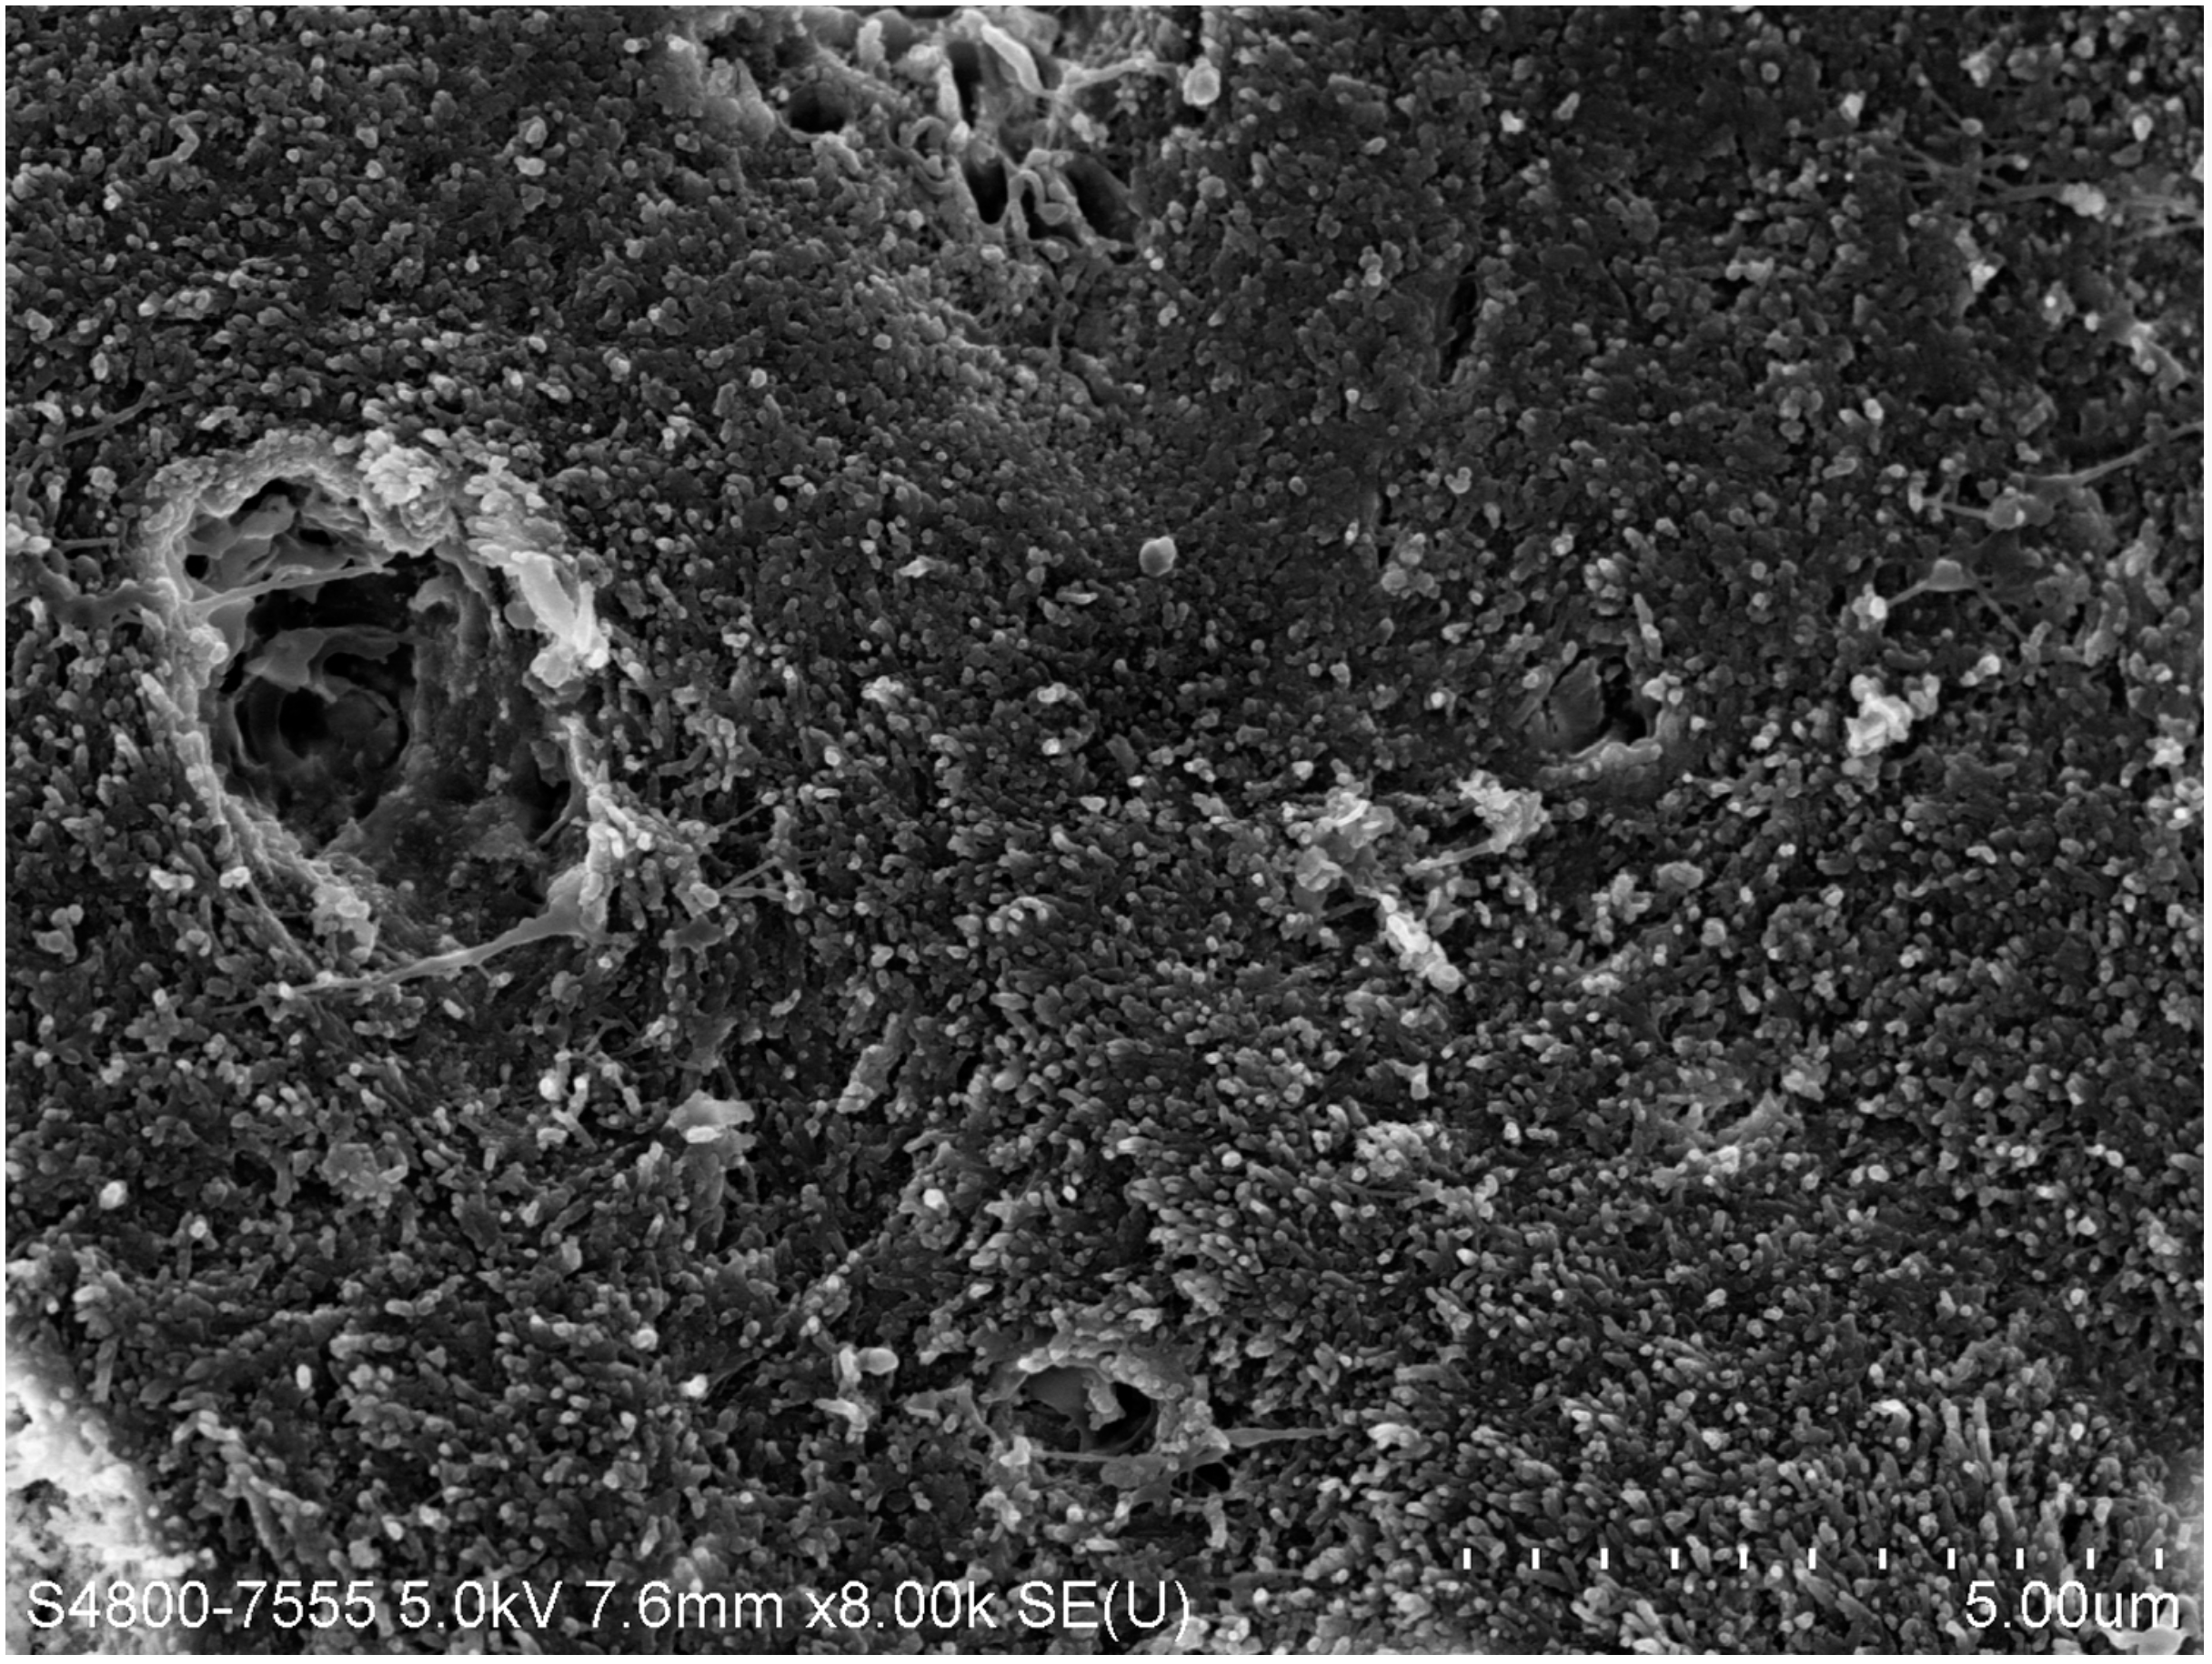

Fig 3. Scanning electron microscope (SEM) images of the dentin carious lesions: surface morphology of arrested carious lesion. (image from Mei, et al, 2014, ref 21 [reprinted with approval])

Figure 3

Fig 4. Scanning electron microscope (SEM) images of the dentin carious lesions: surface morphology of active carious lesion. (image from Mei, et al, 2014, ref 21 [reprinted with approval])

Figure 4

There are several advantages of using SDF in dental treatment. First, it showed an antimicrobial activity against mono-species, dual-species, and multi-species cariogenic biofilm.14-16 Silver ions are bactericidal metal cations that inhibit biofilm formation.17 Studies have indicated that silver interacts with sulfhydryl groups of proteins and DNA, thus altering hydrogen bonding and inhibiting respiratory processes, DNA unwinding, cell-wall synthesis, and cell division.18 At the macro level, these interactions affect bacterial killing and inhibit biofilm formation.17 Second, fluoride promotes caries lesion remineralization. Fluoride has been indicated to react with hydroxyapatite and generate calcium fluoride, which is a reservoir of fluoride, and facilitate further remineralization.19 An ex vivo study reported surface microhardness of the surface layer of the arrested caries after SDF applications was comparable with the unaffected sound dentin20 (Figure 1 and Figure 2). This is consistent with another study, in which a high remineralized zone was observed on the surface of arrested caries from exfoliated teeth with SDF treatment21 (Figure 3 and Figure 4). Third, its application procedures are simple and do not require injection or drilling, and the treatment does not involve expensive support infrastructure equipment such as piped water and electricity. The simplicity of the treatment is conducive to treating caries in apprehensive young children who may have intense dental fear, uncooperative patients with special needs, or elderly patients who have difficulty adapting to traditional dental care. It also allows trained workers to deliver the treatment to people who live in the area but who may not be able to easily access dental service.22 Patient compliance and satisfaction is often good when the patient is provided a clear explanation of the treatment outcome.23,24 Finally, the cost of SDF treatment is low and should be affordable in most communities.